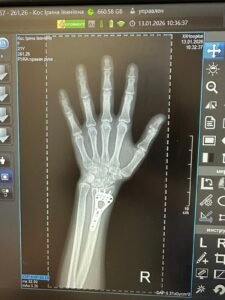

Моє знайомство з Мирославом Ігоровичем відбулося з приводу видалення екстрамедулярного МОС дистального епіметадіафізу правої променевої кістки. Трохи хвилювалась, бо вдруге оперувати руку, коли вже маєш досвід, як це буде – не найприємніше відчуття! Проте, мої страхи були розвіяні, одразу ж, після першої консультації.

Мирослав Ігорович – неймовірна людина та чудовий лікар! Все у нього, якось спокійно, без зайвої метушні, впевнено та професійно. У спілкуванні з лікарем не має відчуття зверхності, як це не рідко трапляється у наш час, а навпаки, щось світле випромінює ця людина!

Щиро дякую, Мирославу Ігоровичу за проведену операцію та косметичний шов! Хай благословенним буде Ваш життєвий та професійний шлях!